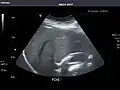

Abdominal Ultrasound (Full Exam)

STRUCTURED REPORT

(Technique: Transabdominal ultrasonography; Device: Toshiba Aplio XG)

Liver: Diffusely homogeneous and normal in echogenicity. No focal mass or contour nodularity. No intrahepatic biliary ductal dilatation.

Portal Vein: Patent main portal vein.

Gallbladder: No stones, wall thickening, or pericholecystic fluid.

Common Bile Duct: Nondilated measuring 1.3 mm at the level of the porta hepatis.

Pancreas: Visualized portions unremarkable.

Spleen: Normal in size.

Kidneys: Right and left kidneys measure 11.5 cm and 12 cm in length respectively. No hydronephrosis. Small left lower pole kidney cyst.

Ascites: None.

Aorta: Visualized portions normal in caliber, 16 x 15 mm.

IVC: Normal.

IMPRESSION:

Normal abdominal ultrasound.